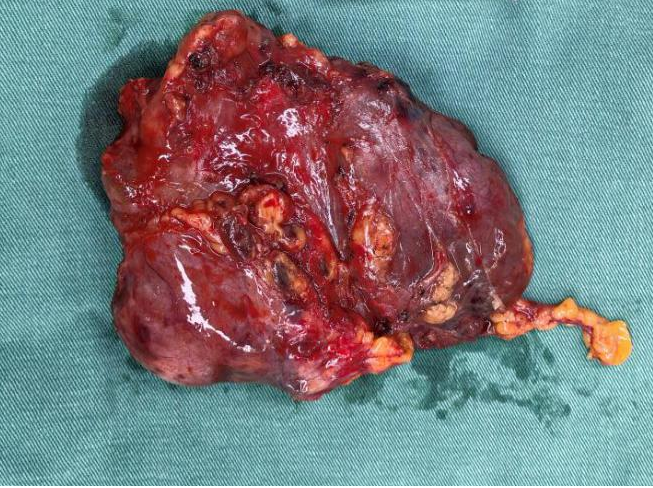

被切除的肿瘤

术前胸心血管外科团队联合多学科评估风险,确定手术方式、风险防范与围手术期应急方案。术中,胸心血管外科副主任吕忠柱主任医师主刀,通过正中胸骨切开手术,凭借精准操作避开致命陷阱,成功拆除前纵隔巨大肿瘤、完成胸腺扩大切除,同时清扫了周围淋巴结,在保证安全的前提下达到了R0切除。手术过程顺利,术后患者顺利脱机拔管,已顺利康复出院。